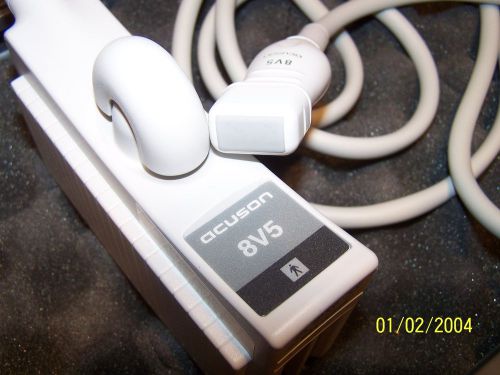

ACUSON 8V5 TRANSDUCER ULTRASOUND PROBE FOR ABDOMINAL, CARDIAC,NEONATAL,PEDIATRIC